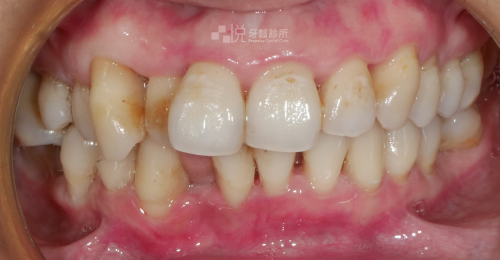

原先有嚴重的牙周病,搭配 4 次的水雷射,約 1 個月的治療時間,就有顯著改善牙周病問題。

舊有假牙侵犯到「生物寬度」(意指假牙邊緣放到牙肉底下太深的位置),導致牙齦有紅腫流血悶痛的發炎反應,本來的牙齒長度偏短、左右牙齦高度不對稱的狀況。

透過【水雷射牙冠增長術】後,讓牙齦恢復健康、和諧的外觀,並完成全口假牙的重建。